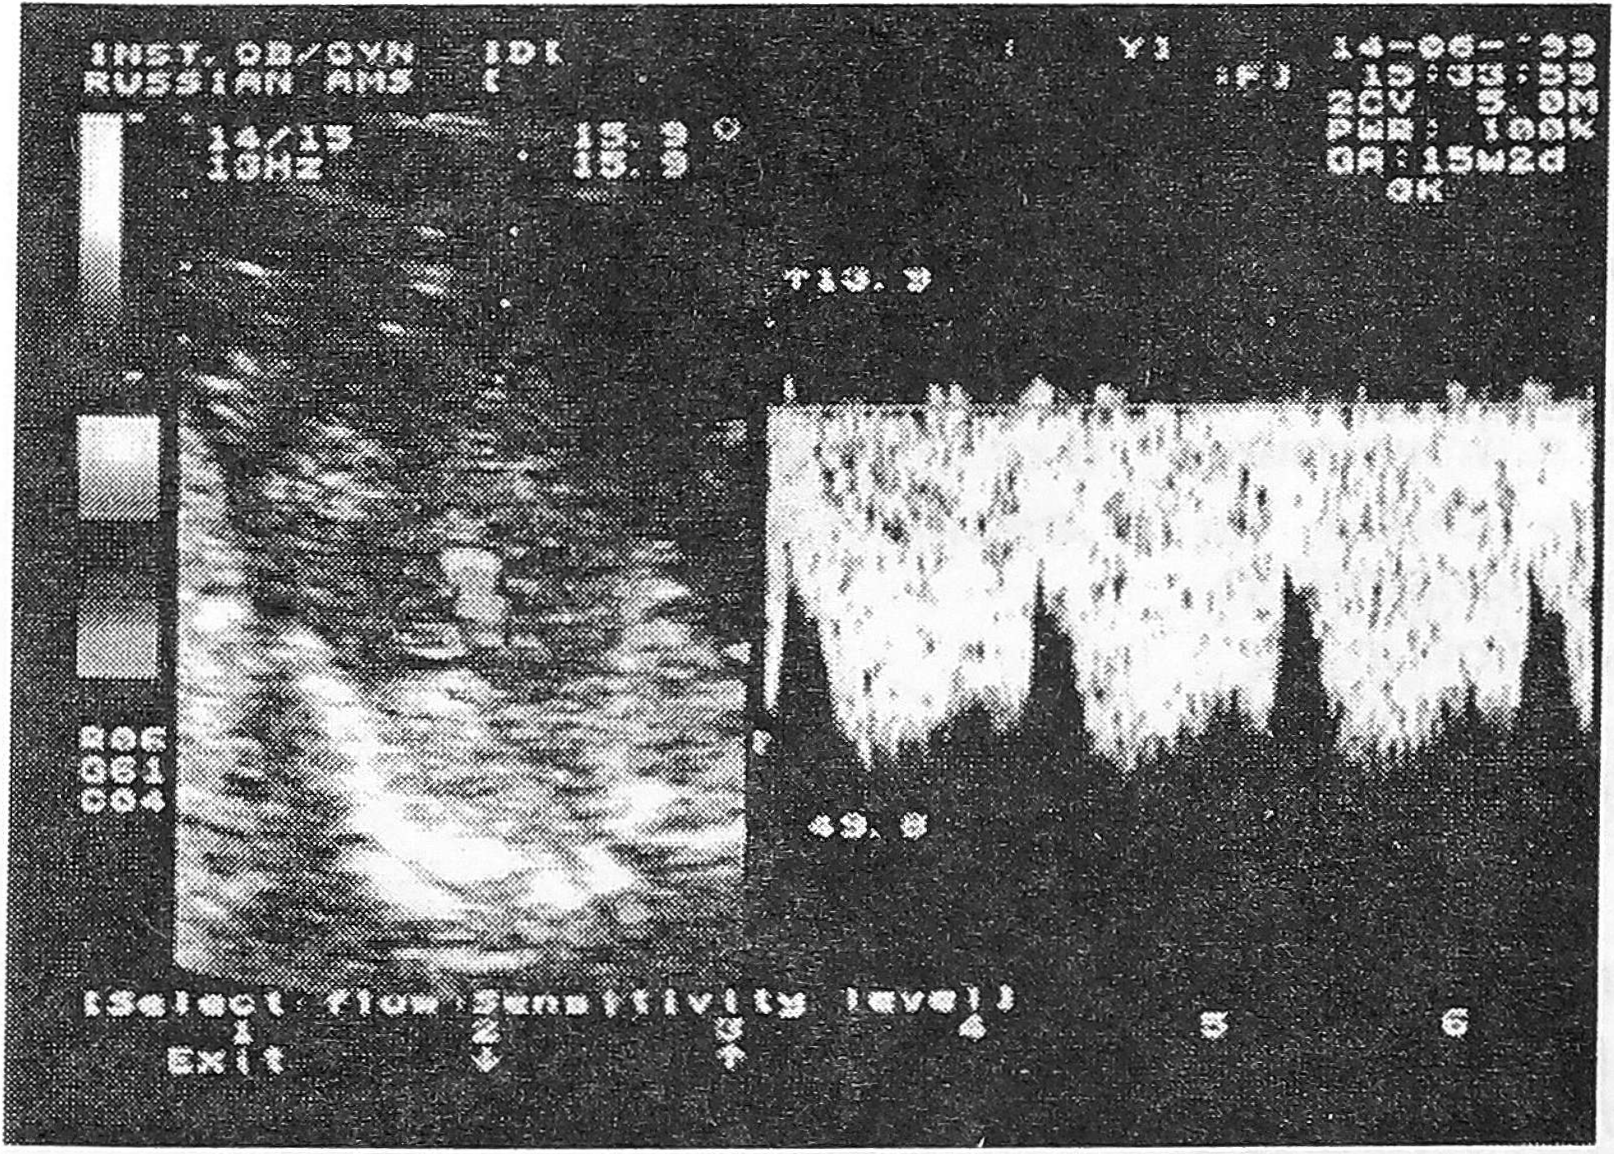

В исследованиях впервые получены данные о кровотоке в яремной вене у плода, по которой осуществляется отток крови из головного мозга. Выявленные особенности становления оттока венозной крови из ЦНС плода совпадают со сроками активности нейроонтогенеза. Так, I-й этап становления гемоциркуляции в яремной вене наблюдается до 32-й недели беременности. В этот период в момент сокращения предсердий плода кровь движется от сердца (регистрируется отрицательный компонент кровотока) (рис. 6). После 32-й недели беременности начинается II этап становления кровотока в яремной вене, во время которого кровь из головного мозга плода оттекает непрерывно на протяжении всех фаз сердечного цикла (рис. 7).

Рис. 6. Допплерограмма кровотока в яремной вене у плода при сроке беременности 24 недели. РК - ретроградный кровоток.